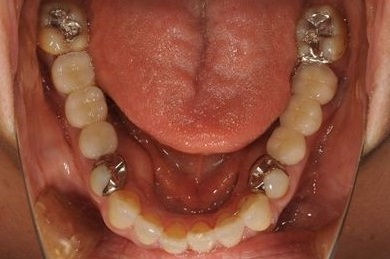

インプラントの症例写真 IMPLANT

抜歯即日スピードインプラント治療

| 性別/年齢 | 女性 / 37歳 | ||||||||||||||||||||||||||||||||

| 主訴 | ブリッジの支えとなっている歯が虫歯になり、ブリッジが難しくなったため、インプラントか義歯かの相談で来院。 | ||||||||||||||||||||||||||||||||

| 治療方針 | 抜歯と同時にインプラント治療を行い、治療期間を短縮する。 | ||||||||||||||||||||||||||||||||

| 治療内容 | インプラント4本(抜歯即日スピードインプラント治療)、ハイブリッドセラミッククラウン6本 | ||||||||||||||||||||||||||||||||

| 総治療費 | 1,236,165円 | ||||||||||||||||||||||||||||||||

| 治療期間 | 1年5ヶ月 |